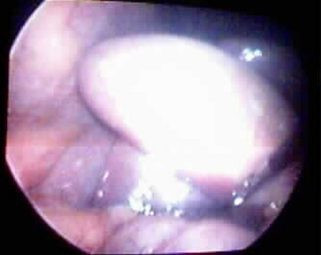

Vesícula y cáncer

Post Image